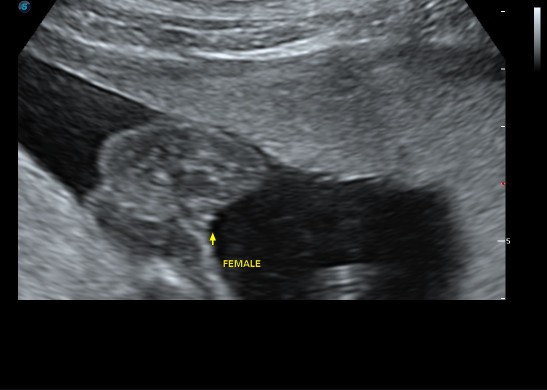

ขอดู รูปซาว หน่อยค่ะว่าเหมื่อนกันไหม หมอ บอกว่า เป็น ญ เพราะไม่มีจู๋โผลมา บ้านอื่น ได้ ญ แบบนี้หรือเปล่าค่ะ แม่แอบกังวล อยากได้ญ กลัว จู่ โผล่มาทีหลัง 😁23+4.